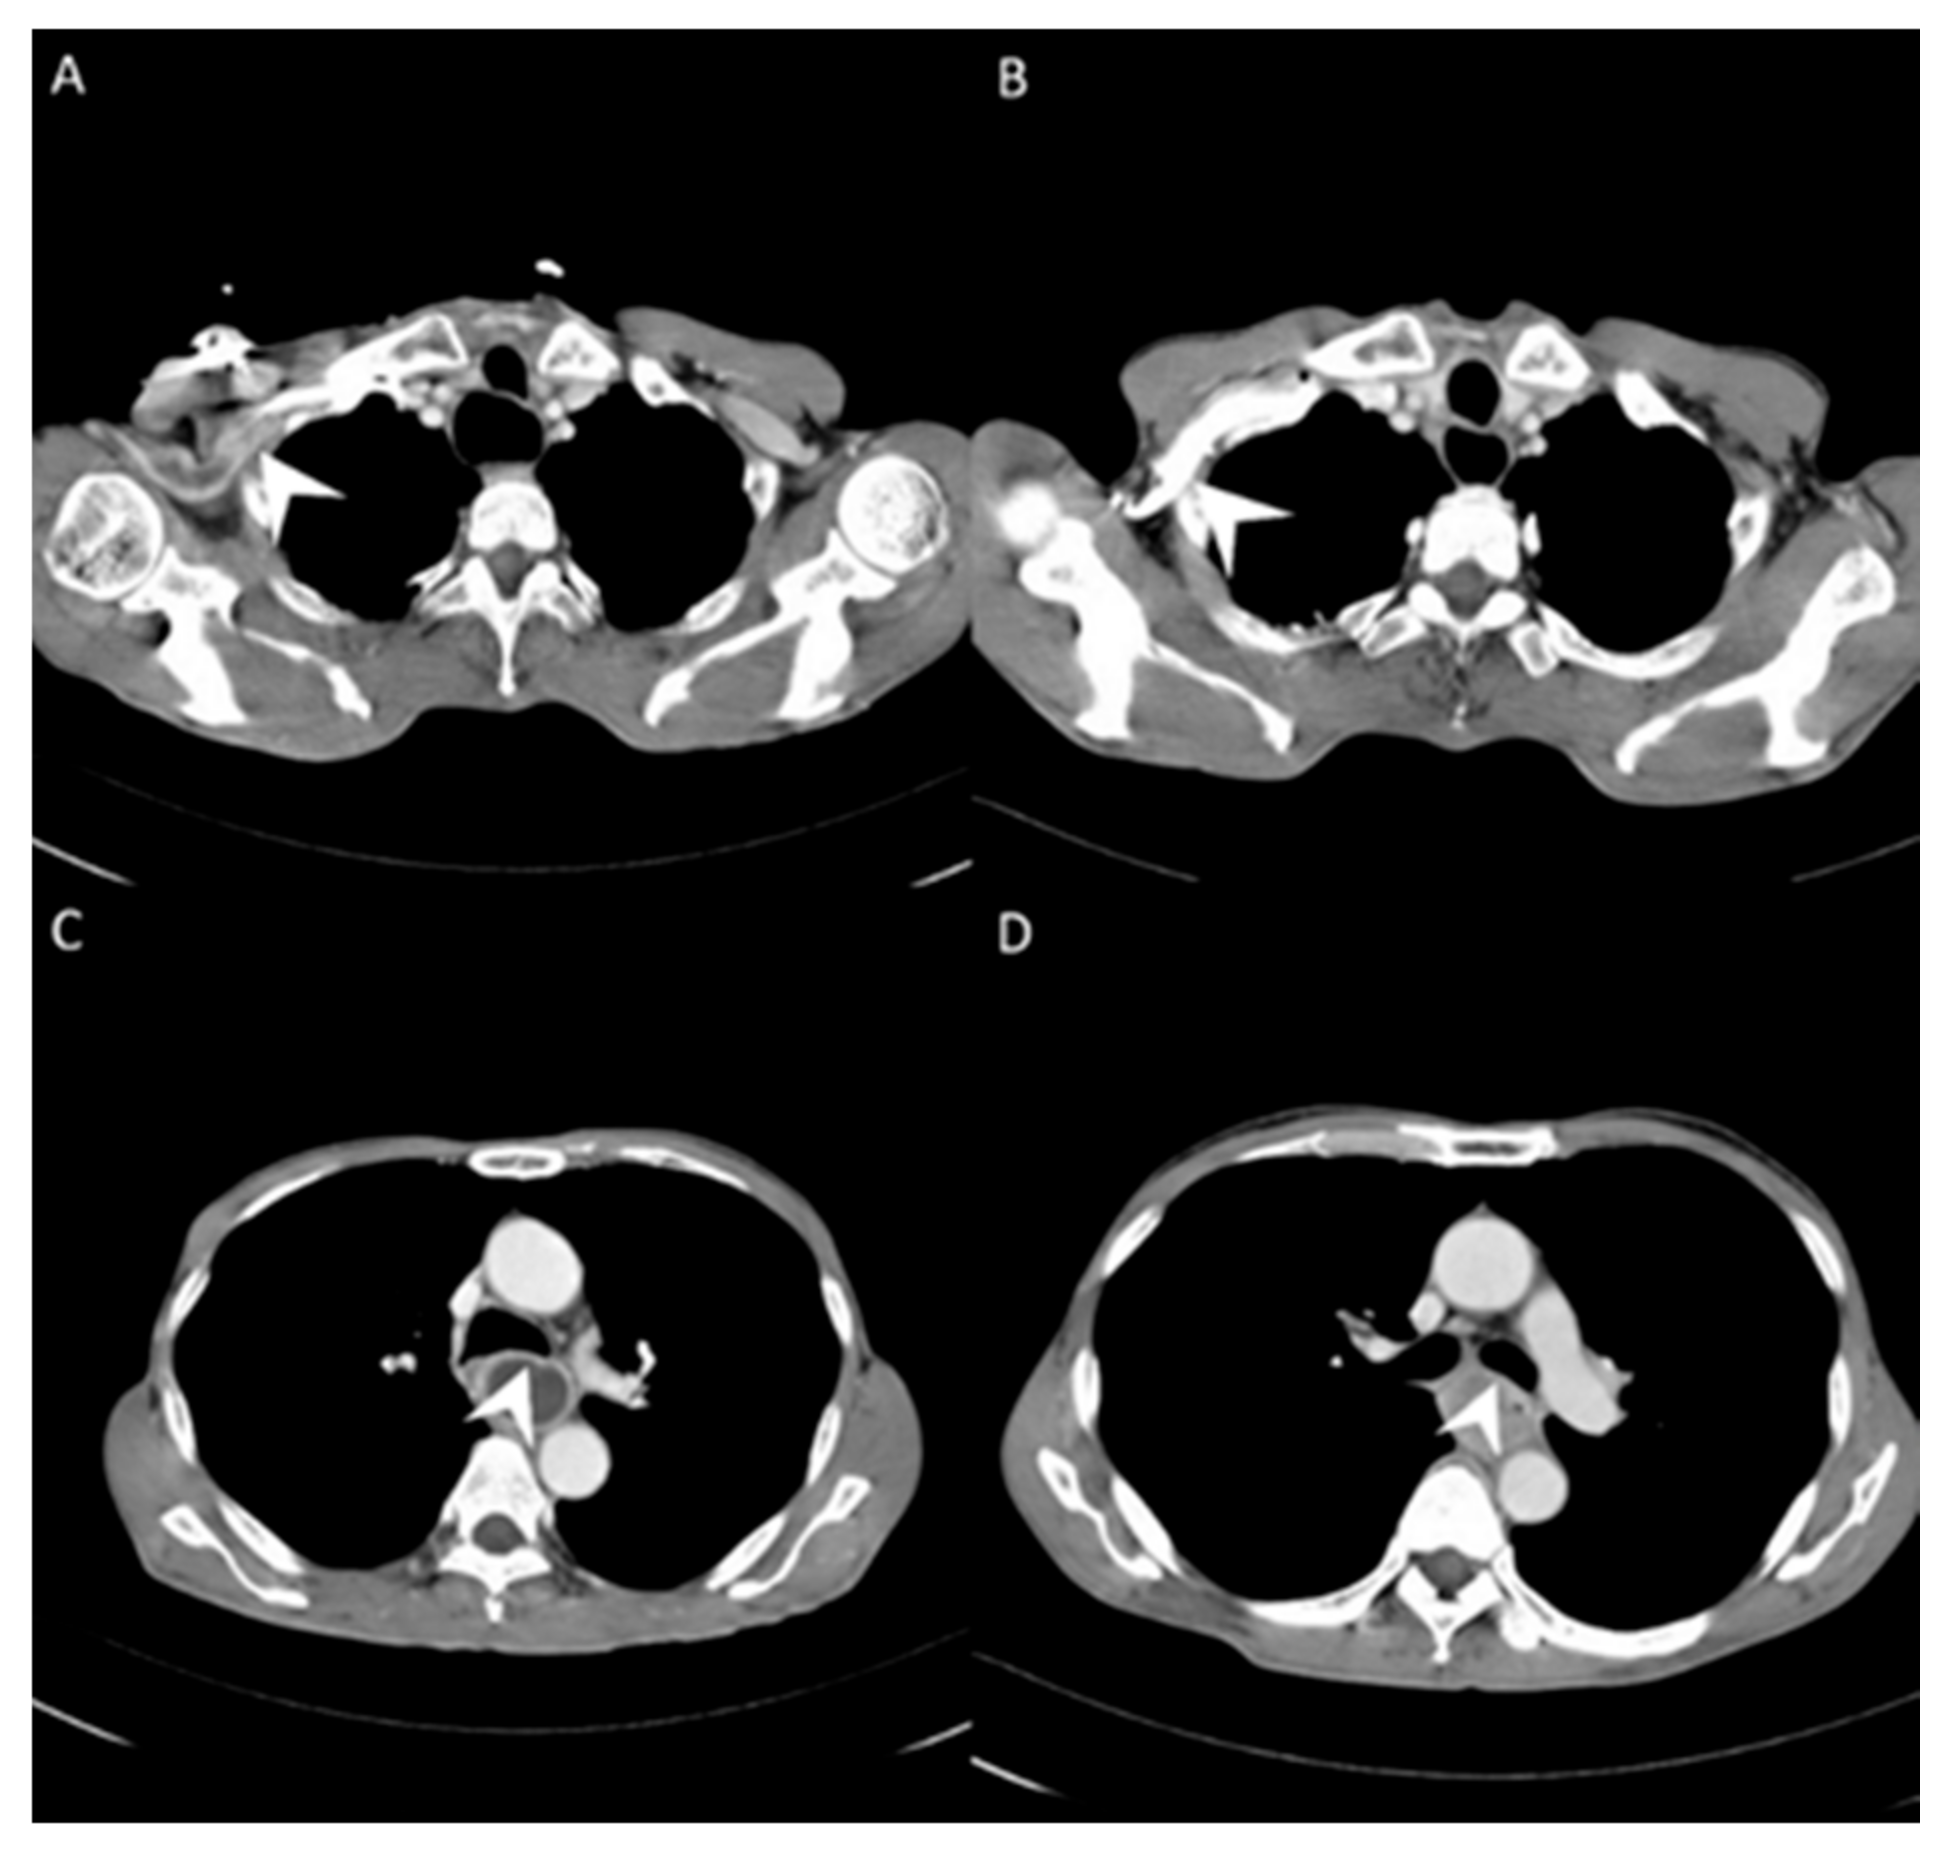

3.1. Image Differences between Central Vein Enhanced and Peripheral Vein Enhanced CT

| Pre-Tx ascending aorta | 189.71 ± 41.43 | 164.97 ± 27.51 | 0.0009 |

| Pre-Tx pulmonary artery | 173.43 ± 42.68 | 156.40 ± 25.07 | 0.0197 |

| Pre-Tx descending aorta | 186.29 ± 39.80 | 163.28 ± 26.12 | 0.0012 |

| Pre-Tx peripheral vein regurgitation | N = 38/Y = 10 | N = 48 | 0.0008 |